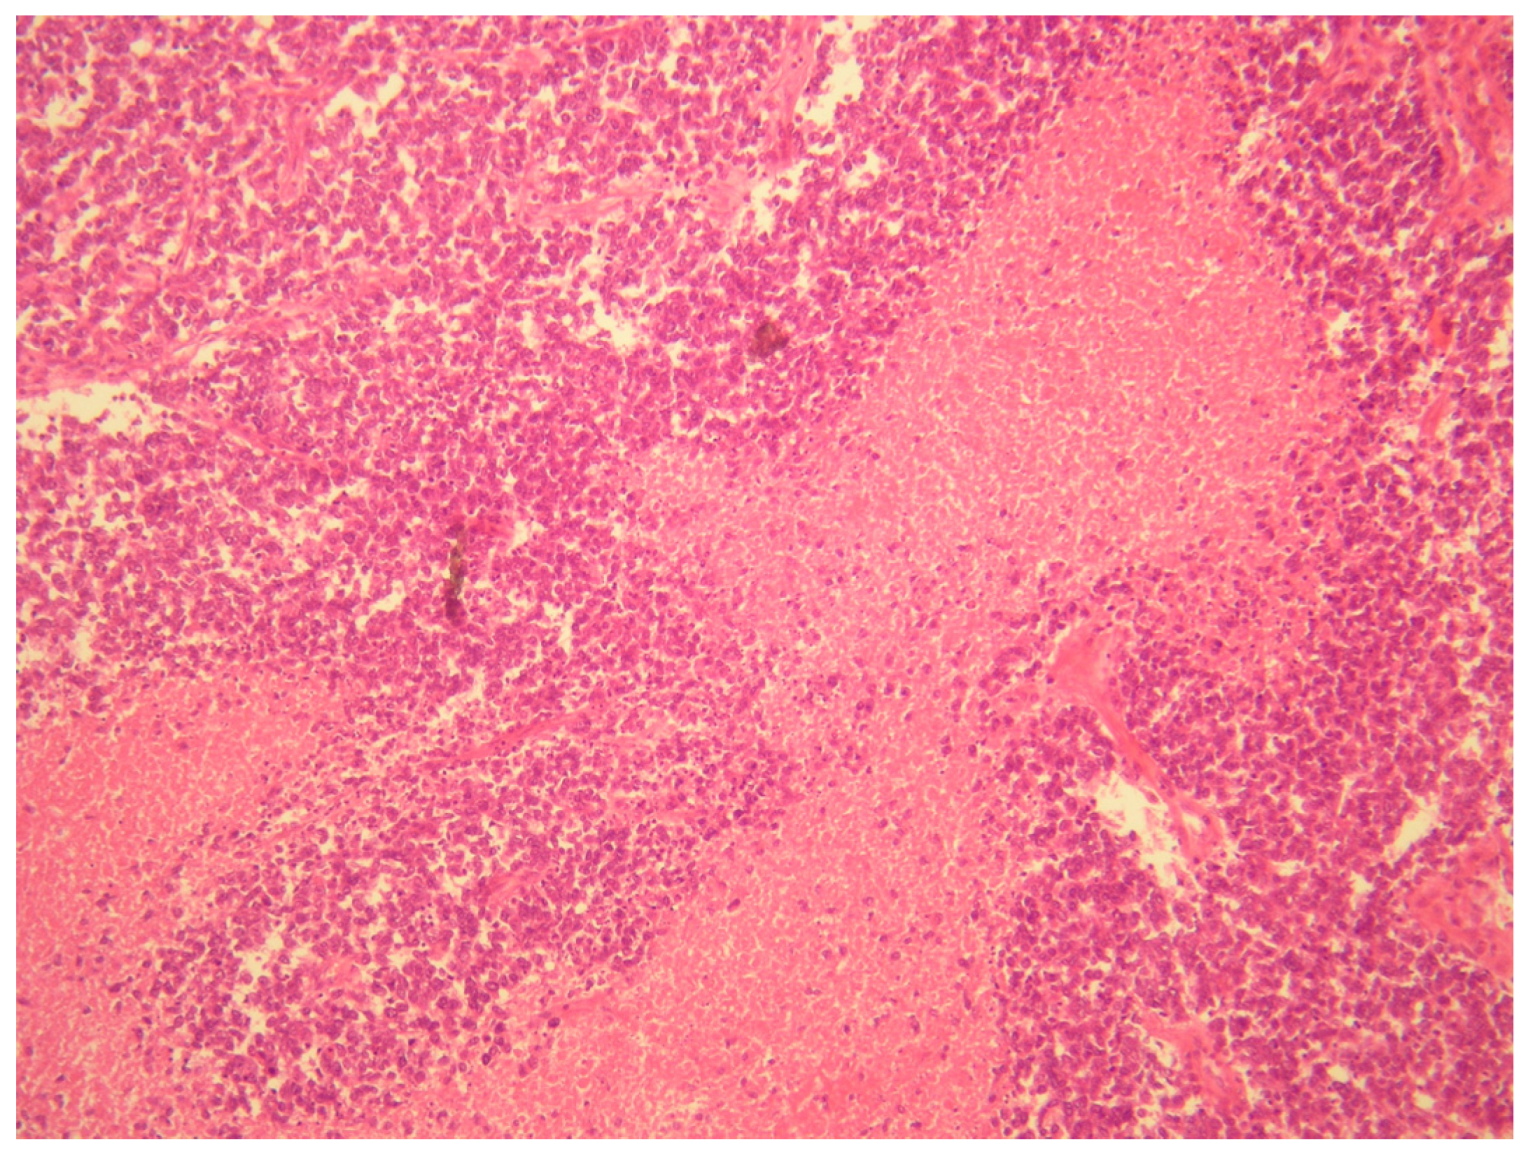

- (1)

- A desmoplastic small round cell tumor (DSRCT), but this was excluded because desmin and WT1 were negative.

- (2)

- Small cell ovarian carcinoma of the hypercalcemic type (OSCCHT), but this was excluded because the ovaries were normal and the tumoral cells were FLI1+ and EMA−.

- (3)

- Metastatic small cells melanoma, but this was also excluded because of the cytokeratin positivity and negativity of HBME-45 and Melan A.

- (4)

- Rhabdomyosarcoma, excludable due to negative muscle markers (desmin, myogenin, myoglobin, MYOD1 and positive anti-cytokeratin antibodies).

- (5)

- Neuroblastoma, excluded due to negative NSE, neurofilament, synaptophysin and positive anti-cytokeratin antibodies.

- (6)

- Juvenile granulosa cell tumor of the ovary, excluded due to the intraoperative findings of normal ovaries and for negative inibin and positive anti-cytokeratin antibodies.

- (7)

- Ewing sarcoma; this was the main one suspected, both for morphological criteria and for immunohistochemistry, too (positive CD99, cytokeratin, vimentin and FLI1).